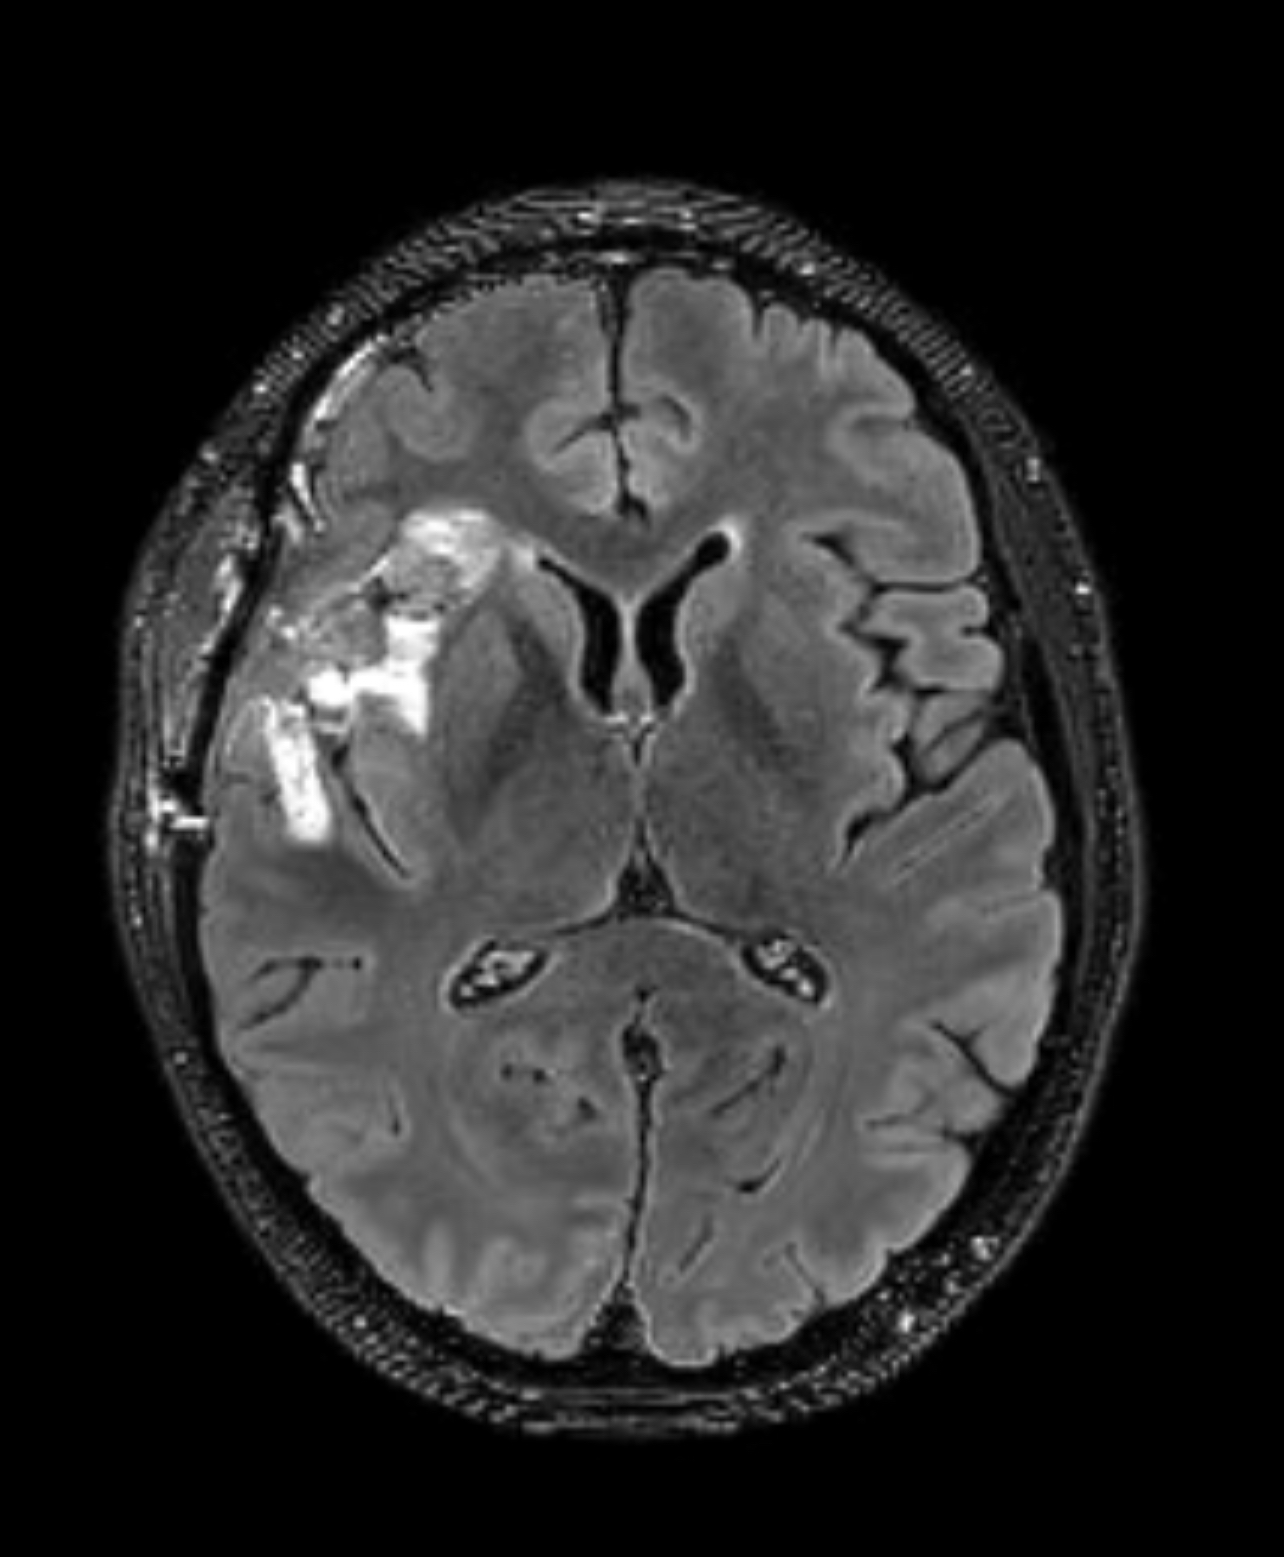

But I am forever the optimist, and I love spreading good news. So, here it is: the spot is GONE! Looking below at the image is a comparison of the October MRI (right pane) with the March one (left pane), an lo-and-behold the spot is nearly gone.

What does this mean? Well, according to the written report of the follow-up visit with the oncologist, this constitutes “remission“. There are no new indications of tumor growth and even the injuries from the treatment are now fading away to nothing.

In the image above, the December MRI (pre-treatment) is on the right side, while the March MRI is on the left side. These two images show that no new cancer is growing, and also that the brain is in process of healing itself: filling in the gap where the tumor was removed.

What you can see here are the side-by-side comparisons of the same kind of scan in the same “slice” (cross-section area of the brain). The scans show NO GROWTH of cancer, and even a small reduction in the amount highlighted by the contrast.